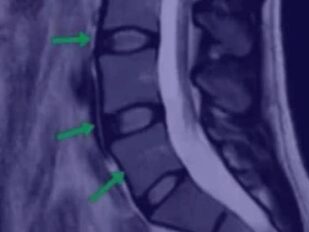

- Что оценивать на МРТ

- Как выглядит идеальный позвоночник

- Как выглядит плохой позвоночник

- Как выглядит позвоночник спортсмена

- Надрыв кольца на МРТ, поясничный прострел

- Протрузия на МРТ

- Грыжа осложненная стенозом канала

- Секвестрированная грыжа

- Артроз на МРТ

- Позвоночник пациента, занимающегося тяжелым физическим трудом

- Остеопороз, перелом позвонка

- Кисты на суставах

- Гипертрофия фасетки

- Листезы

- Гемангиомы

- Гипертрофия желтой связки

- Грыжа Шморля